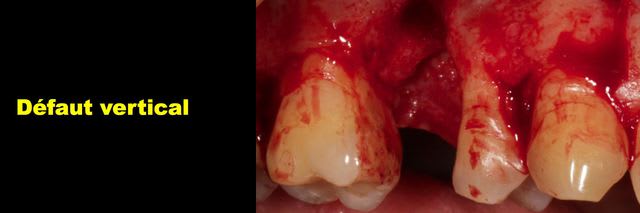

Bon j'ai extrait la dent et maintenant y a un gros trou.

Img 3472 m6qobf - Eugenol

Img 3473 xs5juw - Eugenol